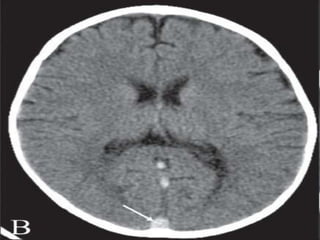

Vascular Insults • SubarachniodHemorrhage. • Lobar and basal ganglia bleeds. • Ischemic strokes. • Venous infarcts. • Disections

• 118.